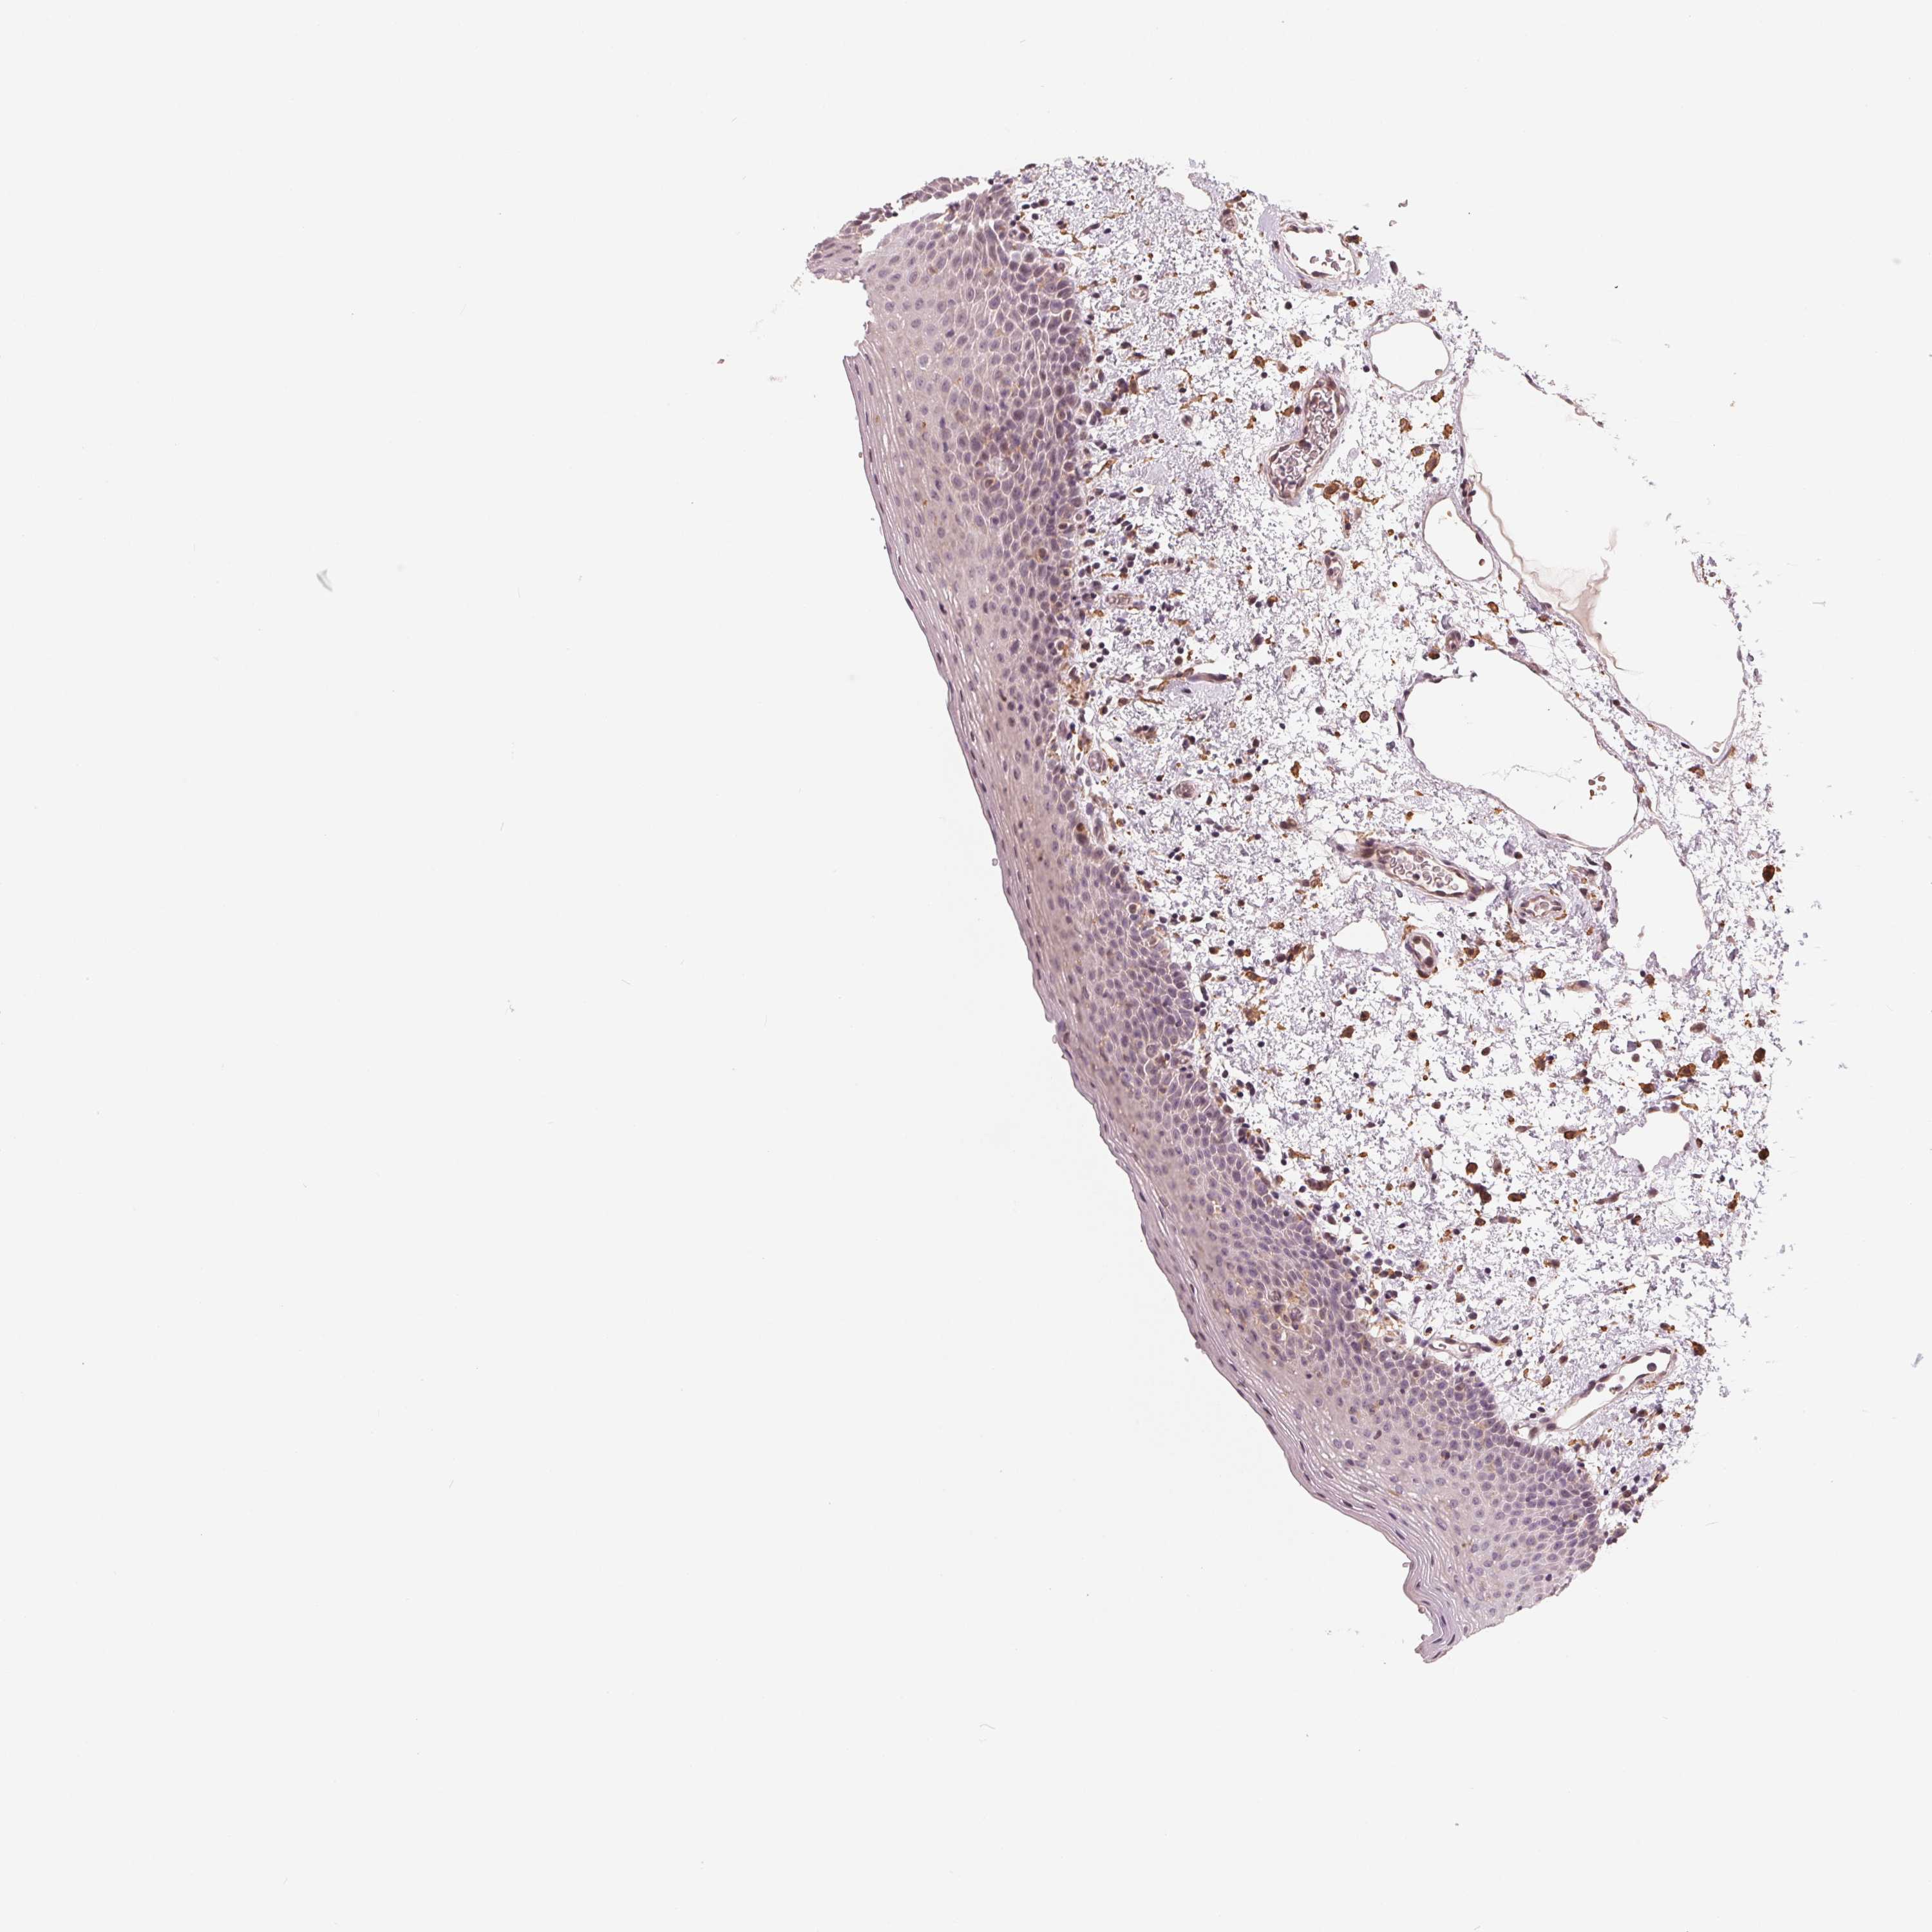

TISSUE PRIMARY DATA ORAL MUCOSA Show tissue menu

ORAL MUCOSA - Antibody stainingi

Antibody staining in the annotated cell types in the current human tissue is reported as not detected, low, medium, or high, based on conventional immunohistochemistry profiling in selected tissues. This score is based on the combination of the staining intensity and fraction of stained cells.

Each image is clickable and will lead to virtual microscopy that enables deeper exploration of all samples and also displays staining intensity scores, fraction scores and subcellular localization as well as patient and tissue information for each sample.

Antibody HPA063240Antibody HPA064557

Squamous epithelial cells Not detectedNot detected